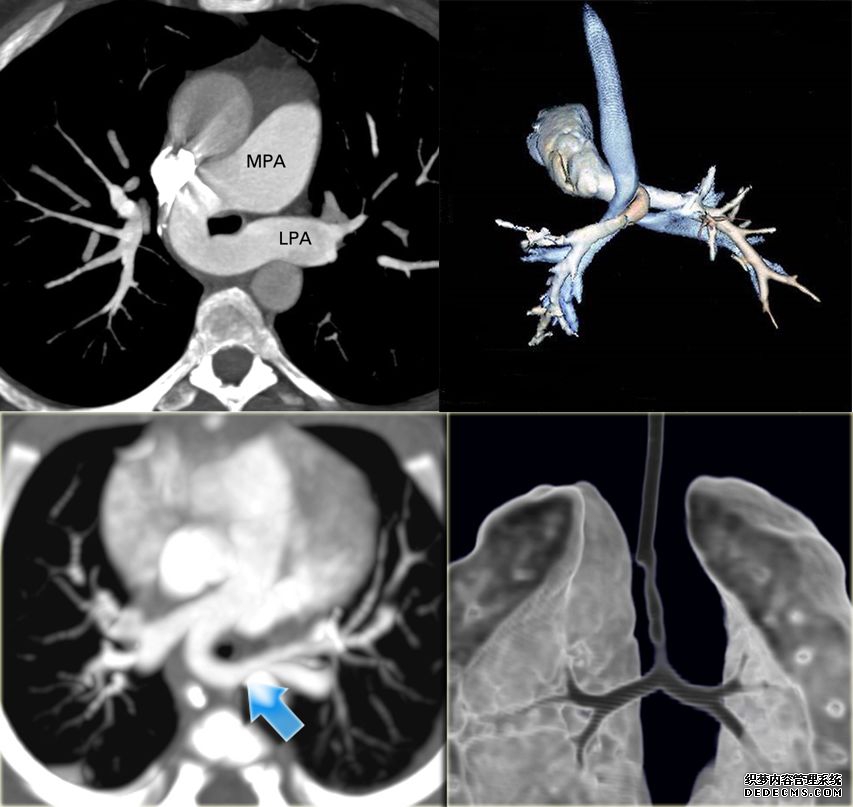

5、MSCT 是诊断该基本的首选手段,能清晰显示周围器官的压迫情况,并能显示肺部及气管、支气管的发育情况,尤其显示气管、支气管的压迫情况及狭窄范围,明确有无气管畸形等。MSCT 及二维和三维重建(VR、MinIP、MPR 等)可清晰显示 PAS 和伴随的气管异常,克服了 DSA 及支气管镜为创伤性检查的缺点,克服了 MRI 扫描时间长,镇静要求高的缺点,并且克服了超声心动图显示大血管欠佳及无法显示气管的缺点。CVE(仿真内窥镜)与支气管检查相仿,均可显示气管的狭窄部位及程度,避免支气管镜检查造成气管梗阻和呼吸道症状加重;